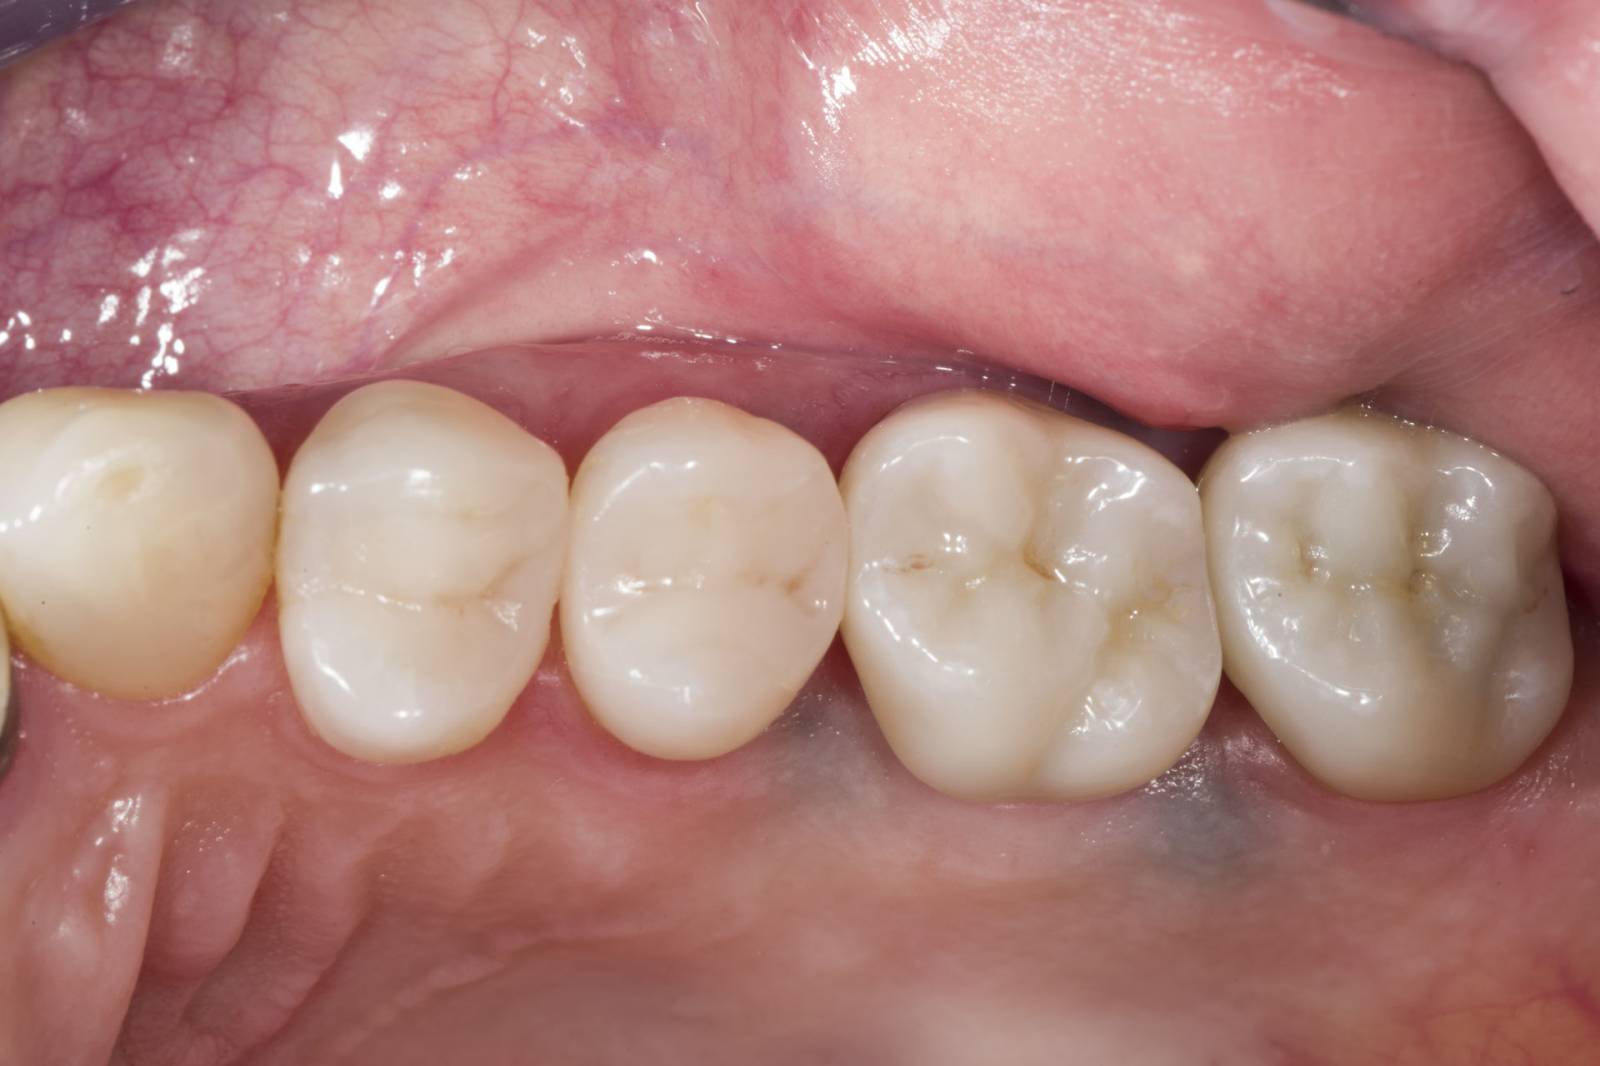

Quadrant rehabilitation

Two CEREC Tessera crowns and two inlays

Within a single visit of four hours the restoration of two crowns and two inlays, which were 15 years old, was carried out. The patient was very pleased with the very good esthetic result.

Before: Insufficient fillings in the second quadrant. The restorations were about 15 years old.

After: Chairside-fabricated crowns made from CEREC Tessera (teeth 26/27). Inlays for teeth 24 and 25 made of composite blocks.

Dr. Andreas Bindl

Zurich, Switzerland